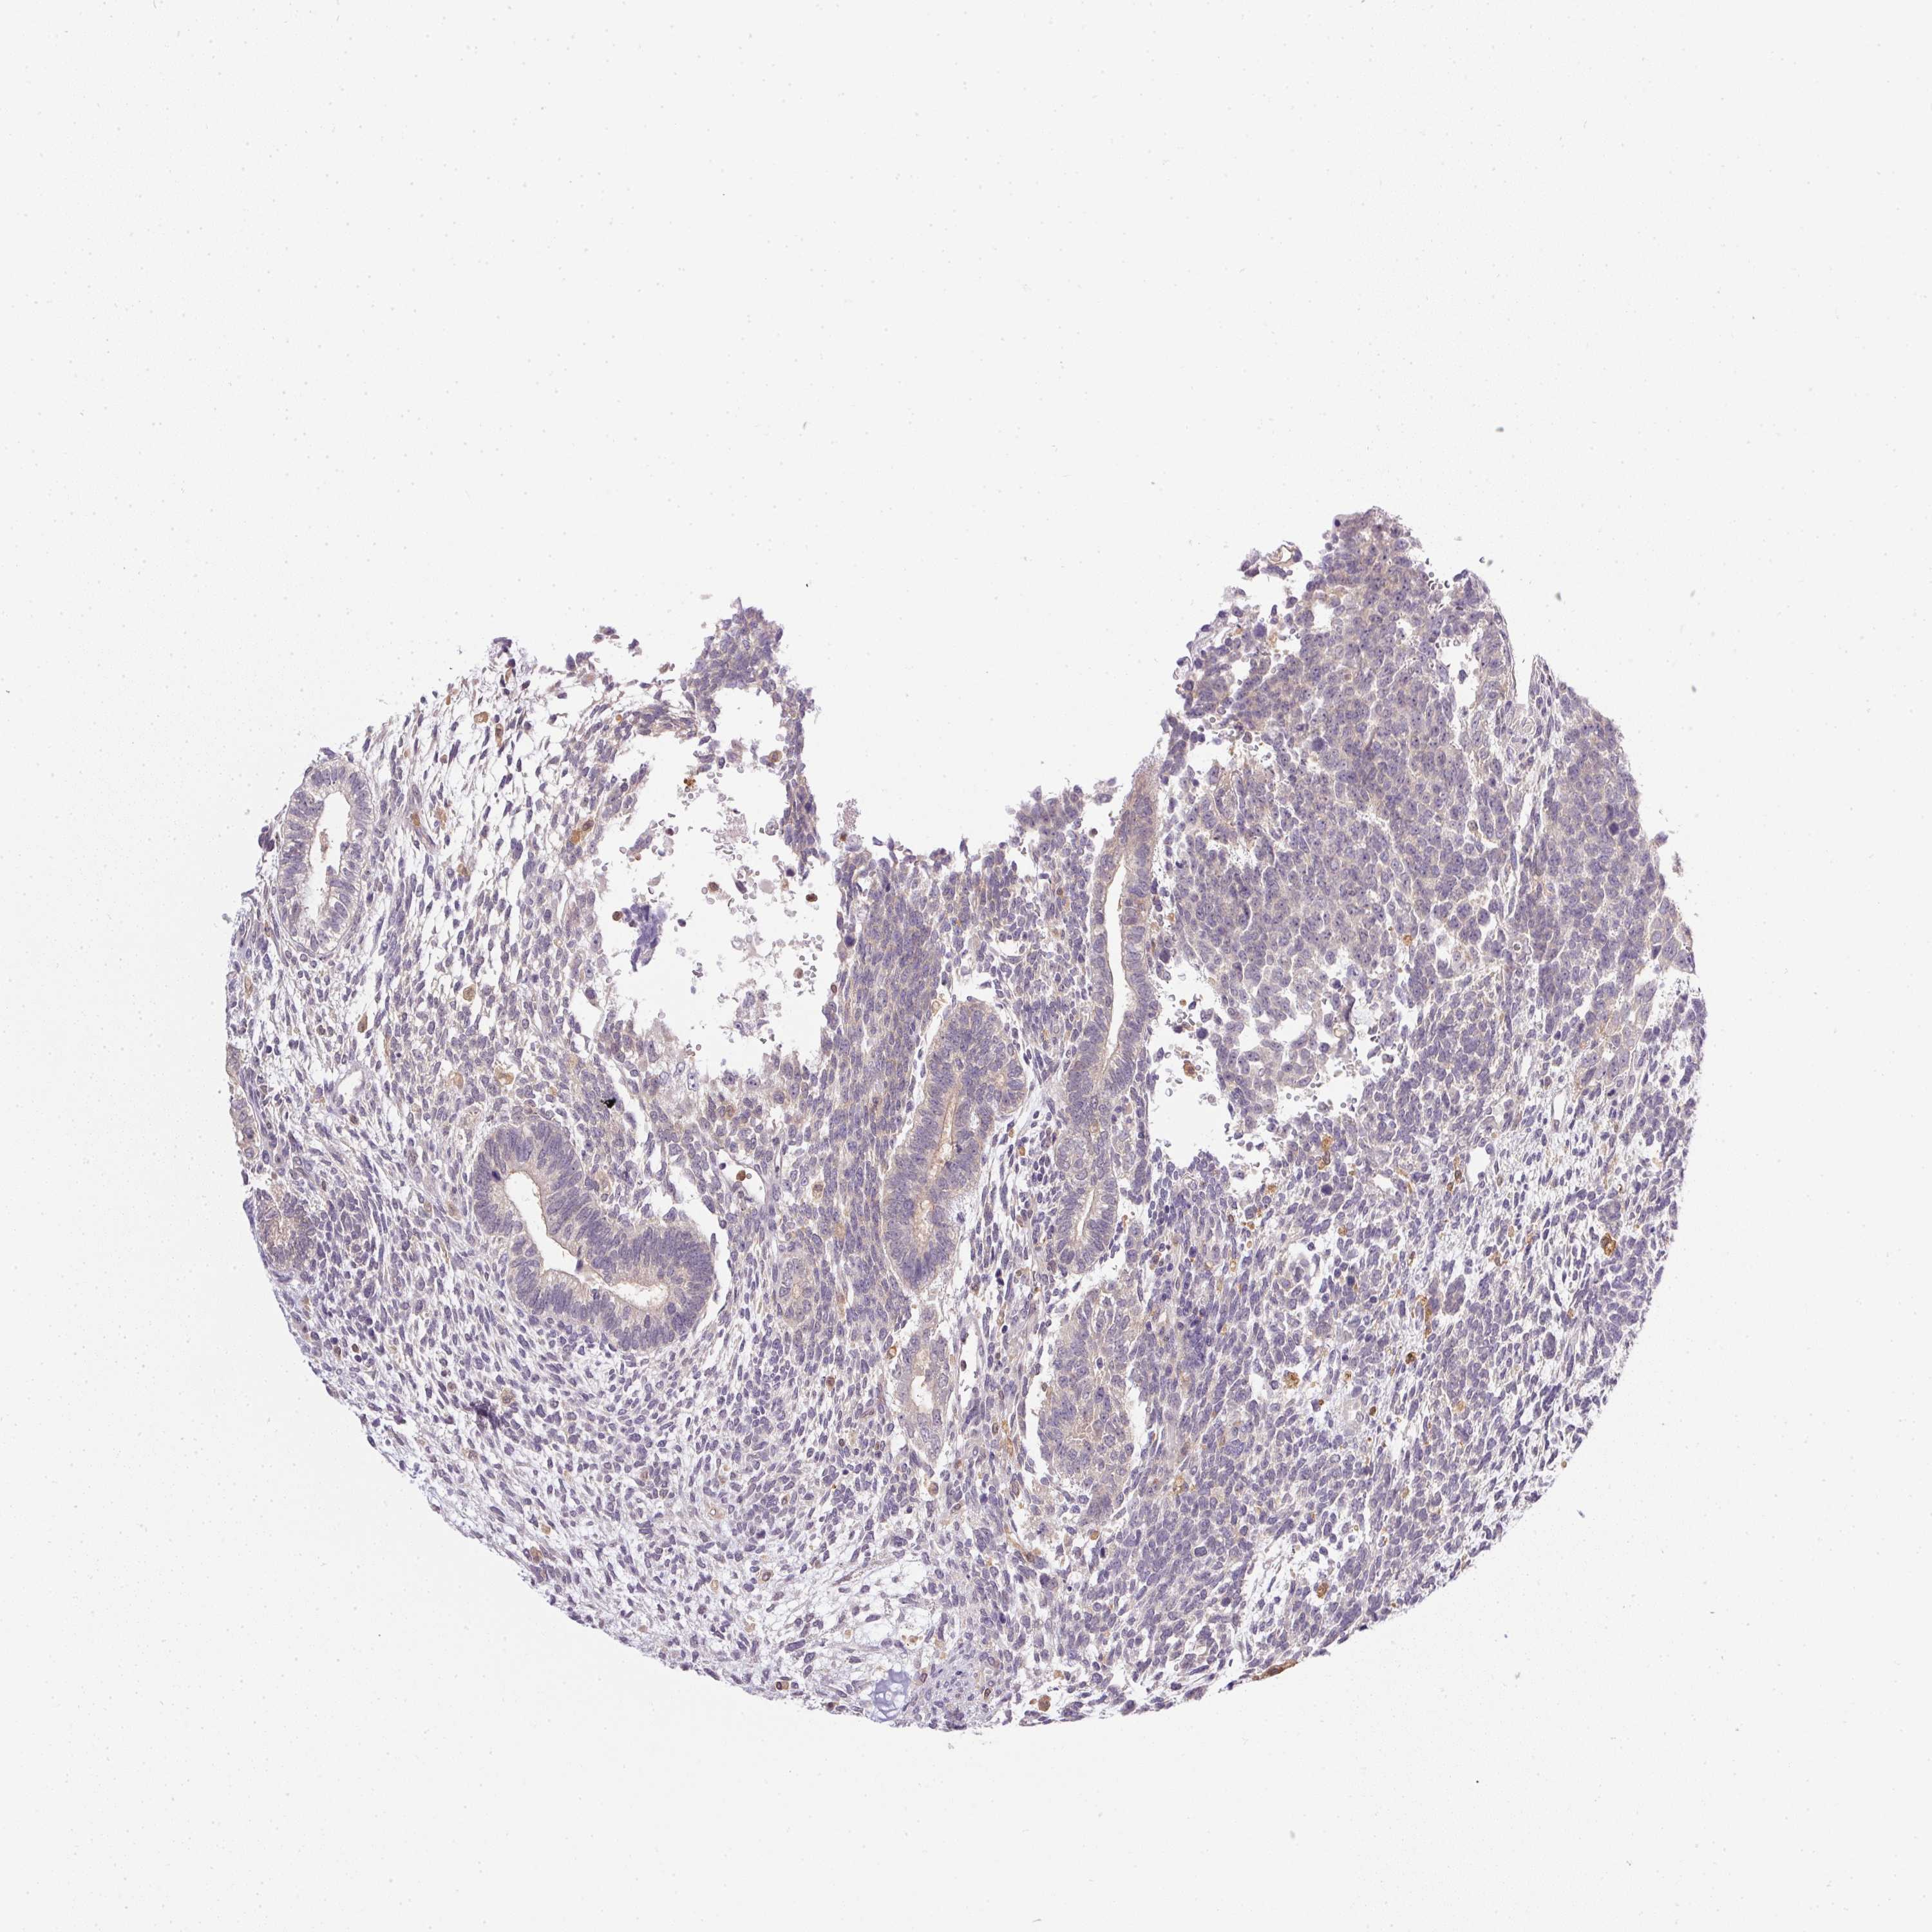

TESTIS CANCER - Protein expressioni

A mouse-over function shows sample information and annotation data. Click on an image to view it in a full screen mode. Samples can be filtered based on level of antibody staining by selecting one or several of the following categories: high, medium, low and not detected. The assay and annotation is described here.

Note that samples used for immunohistochemistry by the Human Protein Atlas do not correspond to samples in the TCGA dataset.

Antibody stainingi

Antibody staining in the annotated cell types in the current human tissue is reported as not detected, low, medium, or high, based on conventional immunohistochemistry profiling in selected tissues. This score is based on the combination of the staining intensity and fraction of stained cells.

Each image is clickable and will lead to virtual microscopy that enables deeper exploration of all samples and also displays staining intensity scores, fraction scores and subcellular localization as well as patient and tissue information for each sample.

Antibody HPA041445

Staining

High

Medium

Low

Not detected

Intensity

Strong

Moderate

Weak

Negative

Quantity

>75%

75%-25%

<25%

None

Location

Nuclear

Cytoplasmic/membranous

Cytoplasmic/membranous,nuclear

Seminoma, NOS

Carcinoma, Embryonal, NOS

Teratoma, malignant, NOS